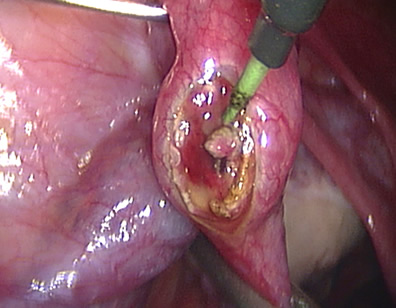

The tube is being opened to reveal the pregnancy